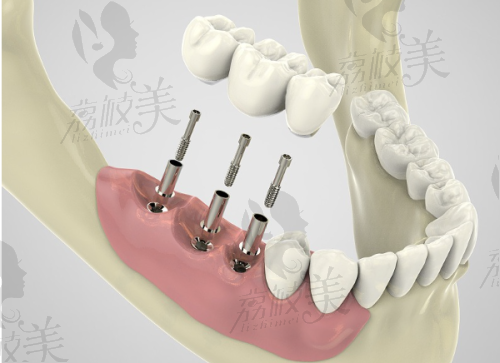

在呀哚口腔,完成“韩系种植牙”大致分为以下几个步骤:

1. 免费口腔拍片与检查:通过全景X光、CBCT立体成像,全方面了解牙槽骨及周围组织情况。

2. 方案制定与种植评估:口腔种植医生结合检查报告,为你量身定制种植方案。

3. 数字化微创植入:在数字导板辅助下,严谨打孔并植入种植体。过程约30分钟。

4. 术后复诊与修复:术后会定期检查种植部位愈合情况,并在术后3~6月安装牙冠。